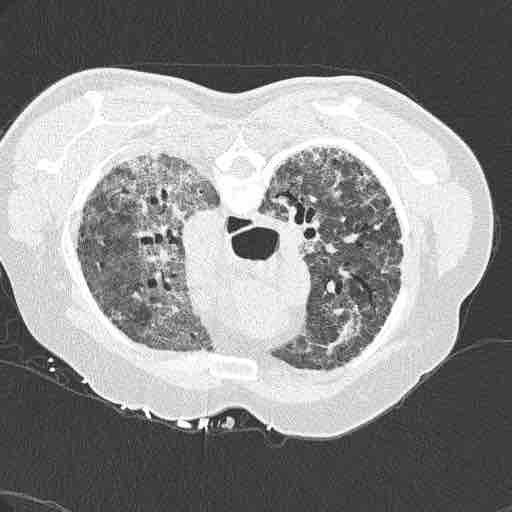

A pulmonologist colleague shows you this CT chest (photo).

70M. CLL. ILD. No Rx.

6w ago: dyspnea, cough, no sputum

Rx: High-dose steroids with prolonged taper for ILD exacerbation. No response.

6d ago: dyspnea worsen. 3L NC to >92% O2 sat.

No fever. Easy fatigability.

Case diagnosis: #Pneumocystis jirovecii pneumonia

Host/risk factor: elderly man. CLL. ILD Rx with steroids.

Diagnostics: BAL PJP smear+ PCR+

Rx: TMP-SMX